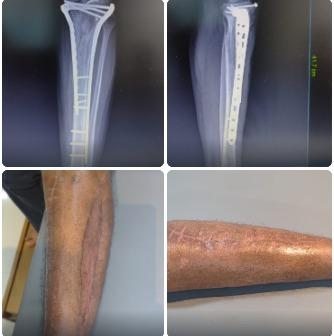

Fracture of Distal end Tibia and Fibula Fixation

Fracture of Distal end Tibia and Fibula Fixation.